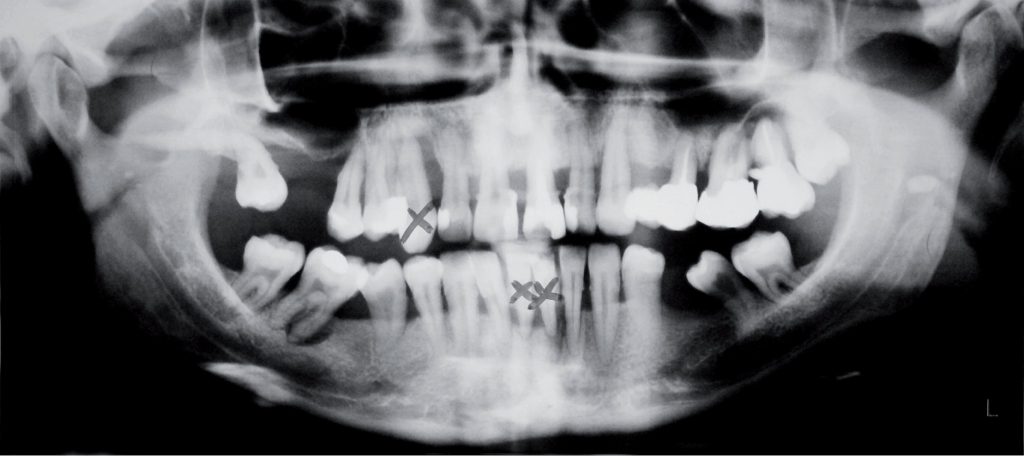

Streszczenie: W artykule przedstawiono interdyscyplinarne leczenie pacjentki z chorobą przyzębia. Opisano wszystkie użyte procedury, niezbędne do uzyskania satysfakcjonującego efektu końcowego, zarówno dla pacjentki, jak i lekarzy prowadzących. W procesie leczenia w celu zmaksymalizowania efektywności zostały wykorzystane najnowocześniejsze metody, m.in. system SAF w leczeniu endodontycznym czy test PET na obecność periopatogenów.

Summary: The article presents interdisciplinary treatment of a patient with periodontal disease. The authors described all stages of treatment, necessary to gain the final effect which would be satisfying for both – a patient and a leading doctor. In this multidisciplinary treatment were used the most modern methods of treatment for the most effective cure: SAF endodontic system and test PET for the presence of periopathogens.

Rehabilitację protetyczną powinniśmy rozpocząć od dokładnego wywiadu, badania zewnątrzustnego [...]